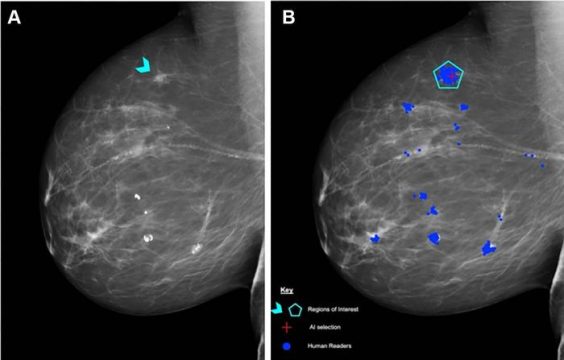

One radiologist supported by AI detected more cases of breast cancer in screening mammography than two radiologists working together, reports the ScreenTrustCAD study from Karolinska Institutet in The Lancet Digital Health. The researchers say that AI is now ready to be implemented in breast cancer screening.

Traditionally, two radiologists read every exam. In the present study, exams were assessed by two radiologists and AI in order to decide which women were to be recalled for further investigation. Based on which women were diagnosed with breast cancer in the end, the researchers could determine how accurate different combinations of AI and radiologists were compared to the traditional two-radiologist approach.

The traditional approach using two radiologists detected 250 cancers. Not unexpectedly, the researchers found that adding AI to two radiologists detected most cases of cancer – 269. One radiologist and AI detected 261 in the same cohort. AI alone detected 246, which was statistically non-inferior to two radiologists.

“Compared with the current two-radiologist standard, assessment by one radiologist and AI resulted in a four per cent increase in breast cancer detection and halved the radiologists’ image reading time,” says principal investigator Fredrik Strand, radiologist and docent at the Department of Oncology-Pathology, Karolinska Institutet.

The researchers also found that compared with two radiologists, one radiologist plus AI and AI alone led, respectively, to a six and 55 per cent reduction in false positives – which is to say the recall rate for healthy women, a procedural error that causes unnecessary suffering and cost.